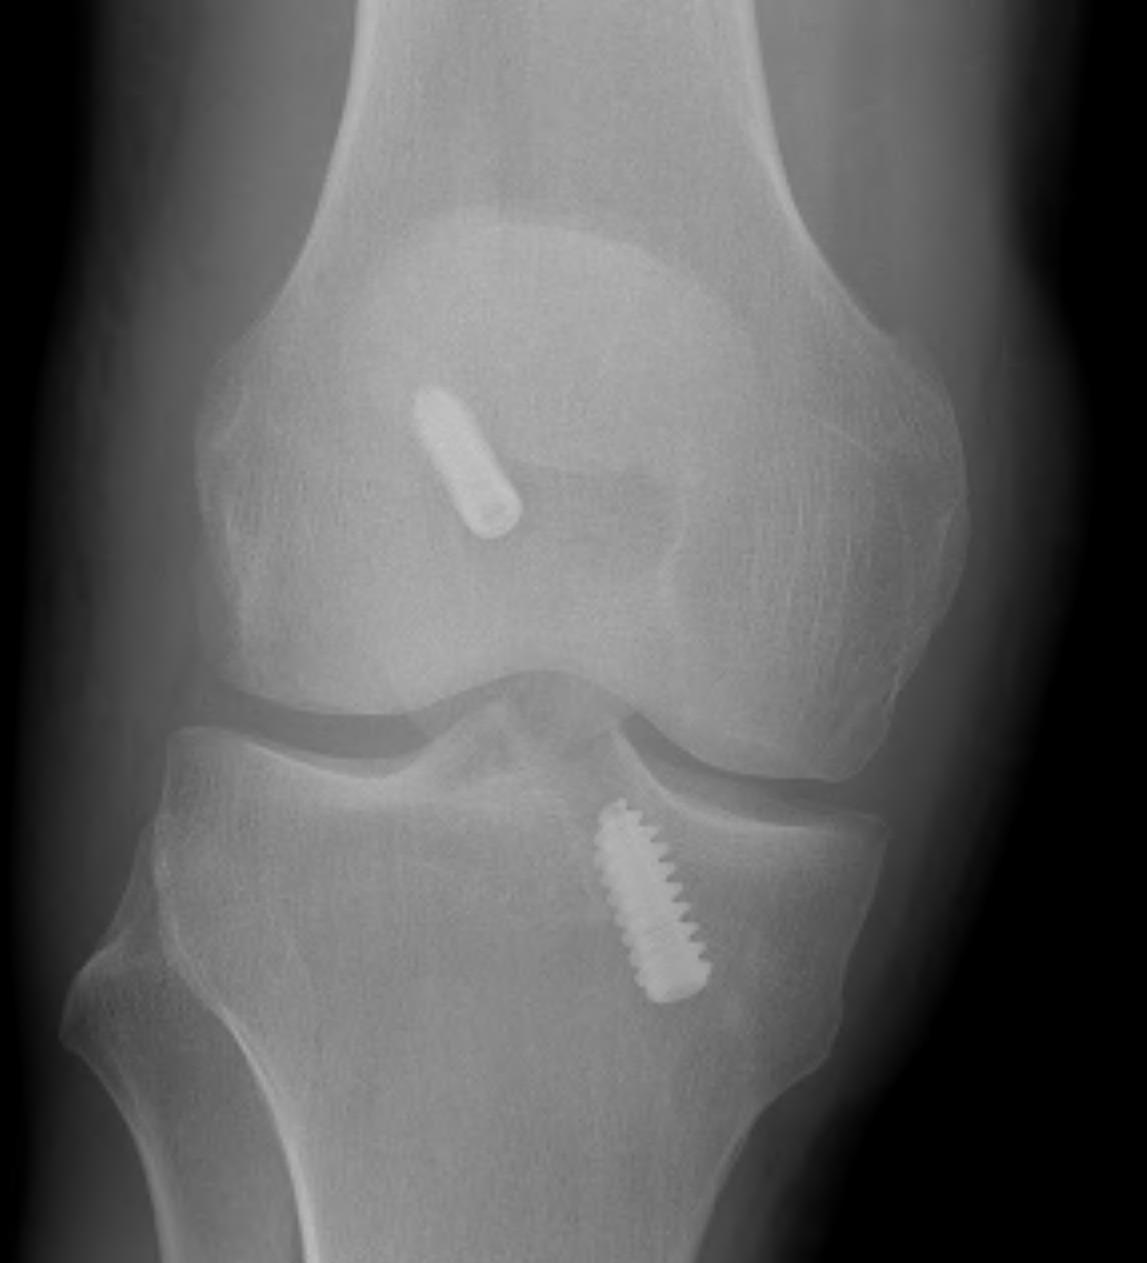

2. X-ray assessment

Lateral x-ray

Femoral tunnel

- intersection of line posterior femoral cortex and Blumensaat's line

Tibial tunnel

- posterior to Blumensaat's line in full extension

- parallel to Blumensaat's line

Pinczewski JBJS Br 2008

- 200 patients followed up over 7 years

1. Posterior femoral tunnel placement

- 86% along Blumensaat's line

2. Anterior tibia tunnel placement

- 48% along tibial plateau

- parallel to Blumensaat's

AP Xray

1. Medial tibial tunnel placement

- 46% (towards medial)

2. Lateral femoral tunnel placement

- 42% from lateral LFC

3. Graft inclination

- 19o

11% rupture rate over 7 years

- associated with posterior tibial tunnel placement

Good rotational stability

- 19o inclination in coronal plane

- avoid too vertical orientation